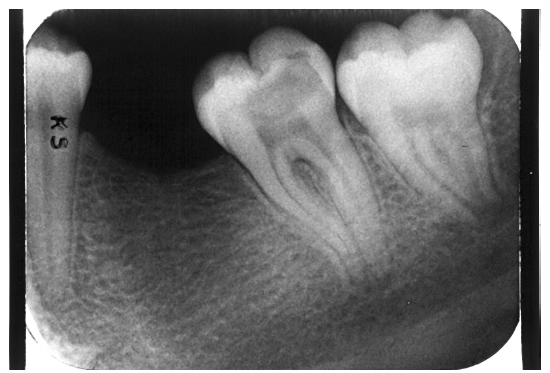

Dentin caries extends into the tooth dentin and can be recognized by noting the focal loss of dentinal radiopacity. Most commonly, this darkened dentin is located beneath carious enamel and, typically, the lateral dimension of the dentinal involvement exceeds that of the associated enamel caries (Figure 3). Dentin caries may be discerned interproximally, on the occlusal surface, buccally/lingually, or on root surfaces.

Figure 3 - Dentin Caries

Figure 3